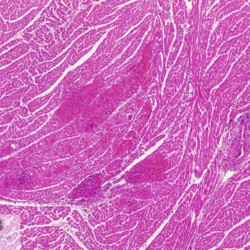

Etiquetes: N-90/90 de 2 Pàgina següent 9 total Canine Specie: Canine Organ: Stomach Lesion: Vasculitis Lesion modifier: - Disease: Leishmaniasis Files/Expedient: N-90/90 Not viewed Canine Specie: Canine Organ: Stomach Lesion: Vasculitis Lesion modifier: - Disease: Leishmaniasis Files/Expedient: N-90/90 Not viewed Canine Specie: Canine Organ: Intestine Lesion: Vasculitis Lesion modifier: - Disease: Leishmaniasis Files/Expedient: N-90/90 Not viewed Canine Specie: Canine Organ: Urinay bladder Lesion: Vasculitis Lesion modifier: - Disease: Leishmaniasis Files/Expedient: N-90/90 Not viewed Canine Specie: Canine Organ: Heart Lesion: Vasculitis Lesion modifier: - Disease: Leishmaniasis Files/Expedient: N-90/90 Not viewed de 2 Pàgina següent Títol Select...Avian (Exotic) (110)Avian (Poultry) (76)Bovine (317)Canine (935)Caprine (47)Equine (257)Feline (326)Ferret (19)General (127)Marine mammal (22)Non-human primate (20)Ovine (328)Porcine (379)Rabbit (61)Reptile (38)Rodent (28)Wildlife (91) Format Select...- (60)Abomasum (37)Adrenal gland (10)Blood (7)Blood vessel (50)Body as a whole (19)Bone (57)Bone marrow (21)Brain (93)Cloaca (1)Diaphragm (2)Ear (5)Esophagus (39)Eye (16)Fetus (12)Gallbladder (23)Gizzard (2)Heart (265)Intestine (356)Joint (32)Kidney (443)Larynx (5)Liver (326)Lung (264)Lymph node (91)Mammary gland (10)Mediastinum (1)Muscle (22)Nasal cavity (22)Nerve (7)Omasum (5)Oral cavity (63)Ovary (14)Oviduct (8)Pancreas (7)Parathyroid (5)Penis (10)Peritoneum (65)Pharynx (9)Pituitary gland (6)Placenta (7)Prostate (8)Proventriculus (3)Reticulum (1)Rumen (28)Sinus (7)Skin (181)Spinal cord (15)Spleen (105)Stomach (125)Teeth (1)Testicle (11)Thoracic cavity (31)Thymus (13)Thyroid gland (5)Tongue (32)Tonsils (11)Trachea (11)Urethra (5)Urinay bladder (61)Uterus (27)Vagina (1)Vulva (1)Yolk sac (1) Cobertura Select...- (152)Abomasitis (26)Abscess (27)Acidosis (1)Adenocarcinoma (20)Adenoma (9)Aerosacculitis (6)Agenesis (1)Agnathia (1)Alopecia (7)Amyloidosis (12)Aneurysm (6)Angiectasis (1)Anthracosis (1)Arteritis (11)Arthritis (15)Arthrogryposis (6)Artifact (4)Ascites (13)Atelectasis (8)Atherosclerosis (5)Atresia (1)Atrial septal defect (2)Atrophy (10)Autolysis (7)Bronchitis (6)Bronchopneumonia (26)Cachexia (2)Carcinoma (103)Cardiomyopathy (19)Cellulitis (2)Chemodectoma (4)Cholangiohepatitis (4)Cholangitis (19)Cholecystitis (4)Cholestasis (5)Chondrodysplasia (2)Chondrosarcoma (2)Chronic passive congestion (13)Chylothorax (2)Cirrhosis (6)Coelomitis (3)Coenurus cerebralis (4)Colitis (40)Congestion (17)Conjunctivitis (5)Coronitis (3)Cryptorchidism (3)Cyst (25)Cystitis (24)Dermatitis (69)Diaphragmatic hernia (4)Dilation (28)Discospondylitis (1)Disseminated intravascular coagulation (7)Dyschondroplasia (1)Dysplasia (29)Ectopia cordis (1)Ectopic ureter (1)Edema (55)Emphysema (5)Encephalitis (5)Endocardiosis (14)Endocarditis (26)Endometritis (5)Enteritis (118)Enterolith (6)Epulis (3)Esophagitis (14)Fasciitis (1)Fibrosis (7)Fibrous osteodystrophy (8)Fistula (1)Folliculitis (3)Fracture (2)Gastritis (34)Gingivitis (5)Glioma (8)Glomerulonephritis (21)Glossitis (25)Glycogenosis (1)Gout (8)Granuloma (2)Granulosa cell tumor (4)Hemangioma (9)Hemangiosarcoma (46)Hematoma (8)Hemoglobinuria (2)Hemopericardium (12)Hemoperitoneum (2)Hemorrhage (100)Hemosiderosis (7)Hemothorax (2)Hepatitis (78)Hernia (11)Histiocytosis (3)Hydatid cyst (11)Hydrocephalus (9)Hydrometra (1)Hydronephrosis (22)Hydropericardium (6)Hydrothorax (3)Hydroureter (5)Hyperkeratosis (8)Hyperostosis (4)Hyperplasia (37)Hypertrophy (9)Hypopigmentation (1)Hypoplasia (7)Hypopyon (1)Impaction (6)Infarction (63)Insulinoma (6)Intussusception (5)Jaundice (17)Laminitis (2)Laryngitis (2)Leiomyoma (5)Leukemia (13)Lipidosis (36)Lipoma (7)Lymphadenitis (45)Lymphadenopathy (7)Lymphangiectasia (6)Lymphangitis (5)Lymphoma (221)Malacia (11)Malignant melanoma (15)Mast cell tumor (11)Mastitis (8)Megaesophagus (2)Melanosis (3)Melena (4)Meningioma (6)Meningitis (6)Meningocele (2)Meningoencephalitis (5)Mesothelioma (5)Methemoglobinemia (2)Mineralization (10)Mucocele (5)Mucometra (1)Multilobular bone tumor (1)Mummification (3)Myelofibrosis (1)Myocarditis (4)Myositis (5)Necrosis (81)Nephritis (113)Nephroblastoma (6)Nephrosclerosis (1)Nephrosis (14)Neuritis (1)Obstruction (13)Omasitis (4)Omphalitis (1)Omphalophlebitis (7)Orchitis (4)Osteoarthrosis (5)Osteomyelitis (9)Otitis (2)Palatoschisis (3)Pancreatitis (3)Panniculitis (3)Papilloma (7)Parakeratosis (14)Patent ductus arteriosus (6)Peliosis hepatis (1)Perforation (17)Pericarditis (35)Peritonitis (39)Persistent right aortic arch (1)Pharyngitis (2)Pheochromocytoma (2)Phlebitis (2)Placentitis (6)Pleuritis (21)Pleuropneumonia (24)Pneumonia (109)Pneumothorax (3)Polycystosis (14)Polyp (5)Polyserositis (6)Posthitis (1)Proctitis (4)Prolapse (3)Prostatitis (3)Proventriculitis (1)Pyelonephritis (24)Pyometra (6)Pyothorax (4)Rhinitis (11)Rumenitis (6)Rupture (24)Salpingitis (3)Sarcoma (57)Sclerosis (1)Scoliosis (2)Seminoma (2)Sequestrum (2)Serous atrophy (14)Sinusitis (7)Splenitis (14)Splenomegaly (9)Spondylitis (6)Spondylosis (1)Stenosis (9)Stomatitis (32)Tenosynovitis (2)Teratoma (3)Thricobezoar (2)Thrombosis (16)Tonsilitis (4)Torsion (13)Tracheitis (4)Tympany (7)Typhlitis (8)Typhlocolitis (4)Ulcer (43)Urethritis (1)Urolithiasis (36)Uroperitoneum (1)Uveitis (1)Vasculitis (15)Ventricular septal defect (3)Volvulus (11) Matèria Select... - (14)- (1653)- (152)Abomasitis - Catarrhal (2)Abomasitis - Catarrhal-hemorrhagic (1)Abomasitis - Chronic (1)Abomasitis - Fibrinous-necrotizing (2)Abomasitis - Hyperplasic (5)Abomasitis - Hyperplasic - Chronic (1)Abomasitis - Necrotic (1)Abomasitis - Necrotizing (2)Abomasitis - Ulcerative (5)Adenocarcinoma (9)Aerosacculitis - Granulomatous (1)Amyloidosis - Chronic (1)Arteritis - Necrotic (2)Arteritis - Necrotizing (1)Arthritis - Chronic (4)Arthritis - Fibrinous-purulent (3)Arthritis - Serous (4)Arthritis - Subacute (1)Ascites - Serous (1)Atrophy - Serous (1)Bronchitis - Catarrhal (3)Bronchitis - Suppurative (1)Bronchopneumonia - Catarrhal-purulent (17)Bronchopneumonia - Fibrinous (1)Bronchopneumonia - Granulomatous (1)Bronchopneumonia - Purulent (1)Bronchopneumonia - Suppurative (5)Carcinoma - Adenocarcinoma (33)Carcinoma - Adenocarcinoma - Hepatocellular (2)Carcinoma - Adenocarcinoma - Mucinous (1)Carcinoma - Basosquamous (1)Carcinoma - Cholangiocellular (3)Carcinoma - Hepatocellular (4)Carcinoma - Metastatic (3)Carcinoma - Squamous cell carcinoma (13)Carcinoma - Transitional cell (2)Cardiomyopathy - Dilated (13)Cardiomyopathy - Hypertrophic (6)Cellulitis - Necrotizing (1)Cholangitis - Chronic (8)Cholangitis - Hyperplasic (3)Cholecystitis - Fibrinous-necrotizing (1)Coelomitis - Fibrinous (1)Coelomitis - Granulomatous (1)Colitis - Catarrhal (3)Colitis - Catarrhal-hemorrhagic (1)Colitis - Fibrinous (1)Colitis - Fibrinous-necrotizing (1)Colitis - Fibrinous-necrotizing (Diphtheritic) (6)Colitis - Granulomatous (2)Colitis - Hemorrhagic (4)Colitis - Hemorrhagic-necrotizing (3)Colitis - Necrotizing (2)Colitis - Ulcerative (6)Congestion - Chronic (2)Conjunctivitis - Hyperplasic (1)Conjunctivitis - Purulent (3)Coronitis - Ulcerative (1)Cystitis - Chronic (3)Cystitis - Fibrinous (1)Cystitis - Fibrinous-necrotizing (1)Cystitis - Follicular (1)Cystitis - Hemorrhagic (6)Cystitis - Hemorrhagic-ulcerative (1)Cystitis - Necrotizing (9)Cystitis - Perforated (1)Dermatitis - Granulomatous (14)Dermatitis - Hyperkeratotic (10)Dermatitis - Hyperplasic (proliferative) (1)Dermatitis - Hyperplastic (10)Dermatitis - Necrotizing (4)Dermatitis - Pustular (4)Dermatitis - Ulcerative (2)Dilation - Chronic (1)Discospondylitis - Necrotizing (1)Dysplasia - Follicular (5)Edema - Interstitial (6)Emphysema - Interstitial (1)Encephalitis - Granulomatous (1)Encephalitis - Nonsuppurative (1)Endocardiosis - Mitral (7)Endocardiosis - Mitral - Chronic (5)Endocarditis - Valvular (6)Endocarditis - Valvular - Mitral (7)Endocarditis - Valvular - Pulmonic (1)Endocarditis - Valvular - Subacute (1)Endocarditis - Valvular - Subaortic (5)Endocarditis - Valvular - Tricuspid (4)Endometritis - Purulent (3)Endometritis - Purulent-hemorrhagic (2)Enteritis - Catarrhal (23)Enteritis - Catarrhal - Acute (1)Enteritis - Catarrhal-hemorrhagic (5)Enteritis - Catarrhal-hemorrhagic - Acute (2)Enteritis - Fibrinous (16)Enteritis - Fibrinous - Acute (3)Enteritis - Fibrinous-necrotizing (7)Enteritis - Granulomatous (14)Enteritis - Granulomatous - Chronic (1)Enteritis - Granulomatous - Multifocal (1)Enteritis - Hemorrhagic (17)Enteritis - Hemorrhagic - Acute (1)Enteritis - Hemorrhagic-necrotizing (1)Enteritis - Hyperplasic (proliferative) (4)Enteritis - Necrotizing (4)Enteritis - Necrotizing - Acute (1)Enteritis - Necrotizing - Hemorrhagic (1)Enteritis - Necrotizing-ulcerative (2)Enteritis - Ulcerative (1)Enteritis - Ulcerative-hemorrhagic (1)Esophagitis - Erosive-ulcerative (6)Esophagitis - Necrotizing (4)Esophagitis - Ulcerative (1)Esophagitis - Ulcerative-necrotizing (1)Fasciitis - Fibrinous-purulent (1)Folliculitis - Purulent (2)Gastritis - Catarrhal (2)Gastritis - Chronic (1)Gastritis - Follicular (1)Gastritis - Hemorrhagic (2)Gastritis - Hemorrhagic-necrotizing (1)Gastritis - Hypertrophic (2)Gastritis - Inclusion bodies (1)Gastritis - Mineralization (1)Gastritis - Mycotic (1)Gastritis - Necrotizing (2)Gastritis - Ulcerative (6)Gastritis - Uremic (3)Gingivitis - Erosive (2)Gingivitis - Hyperplasic (proliferative) (1)Gingivitis - Necrotizing (1)Glomerulonephritis - Chronic (7)Glomerulonephritis - Membranoproliferative (3)Glomerulonephritis - Membranoproliferative - Chronic (1)Glomerulonephritis - Membranous (3)Glomerulonephritis - Membranous - Chronic (1)Glomerulonephritis - Proliferative (2)Glomerulonephritis - Subacute (1)Glossitis - Erosive (2)Glossitis - Granulomatous (6)Glossitis - Hyperplasic (1)Glossitis - Hyperplasic (proliferative) (2)Glossitis - Hyperplastic (1)Glossitis - Necrotizing (2)Glossitis - Necrotizing - Focal (1)Glossitis - Ulcerative (6)Glossitis - Ulcerative - Multifocal (1)Glossitis - Ulcerative - Subacute (1)Glycogenosis (1)Granuloma - Eosinophilic (1)Hemangiosarcoma - Metastatic (2)Hemorrhage - Acute (1)Hemorrhage - Subcapsular (3)Hepatitis - Abscess (9)Hepatitis - Acute (3)Hepatitis - Chronic (4)Hepatitis - Chronic interstitial (6)Hepatitis - Granulomatous (7)Hepatitis - Interstitial - Multifocal (1)Hepatitis - Interstitial - Subacute (1)Hepatitis - Necrotizing (17)Hepatitis - Necrotizing - Acute (2)Hepatitis - Necrotizing - Hemorrhagic (1)Hepatitis - Necrotizing - Subacute (1)Hepatitis - Pyogranulomatous (7)Hepatitis - Subacute (4)Hydronephrosis - Chronic (1)Hydropericardium - Chronic (1)Hyperplasia - Erythroid (1)Hyperplasia - Lymphoid (3)Hyperplasia - Myeloid (1)Hyperplasia - Nodular (8)Hypertrophy - Concentric (2)Hypertrophy - Eccentric (3)Infarction - Acute (17)Infarction - Acute - Multifocal (2)Infarction - Chronic (5)Infarction - Chronic - Multifocal (1)Infarction - Subacute (18)Infarction - Subacute - Focal (2)Laminitis - Chronic (2)Laryngitis - Necrotic (1)Laryngitis - Necrotizing (1)Leukemia - Lymphoid leukemia (2)Leukemia - Non-lymphoid leukemia (6)Lipidosis - Multifocal (1)Lipidosis - Panlobular (1)Lipidosis - Panlobular - Generalized (2)Lymphadenitis - Granulomatous (24)Lymphadenitis - Granulomatous - Chronic (3)Lymphadenitis - Hemorrhagic (1)Lymphadenitis - Necrotizing (5)Lymphadenitis - Necrotizing (caseous) (11)Lymphangitis - Granulomatous (1)Lymphangitis - Purulent (1)Lymphangitis - Ulcerative (1)Lymphoma - Alimentary lymphoma (7)Lymphoma - Cutaneous lymphoma (6)Lymphoma - Lymphosarcoma (2)Lymphoma - Mediastinal lymphoma (1)Lymphoma - Multicentric lymphoma (29)Malignant melanoma - Malignant (1)Malignant melanoma - Metastatic (1)Mast cell tumor - Metastatic (1)Mastitis - Fibrinous-purulent (2)Mastitis - Necrotic (1)Mastitis - Purulent (3)Mastitis - Suppurative (1)Meningitis - Fibrinous-purulent (2)Meningitis - Purulent (4)Meningoencephalitis - Necrotizing (3)Meningoencephalitis - Nonsuppurative (2)Mineralization - Metastatic (4)Myocarditis - Fibrous - Chronic (1)Myocarditis - Granulomatous (1)Myositis - Purulent (2)Necrosis - Acute (1)Necrosis - Cortical (5)Necrosis - Follicular (1)Necrosis - Papillary (8)Necrosis - Papillary - Acute (3)Necrosis - Subacute (3)Necrosis - Tubular (6)Nephritis - Embolic (2)Nephritis - Embolic suppurative (7)Nephritis - Granulomatous (27)Nephritis - Granulomatous - Chronic (1)Nephritis - Granulomatous - Multifocal (1)Nephritis - Interstitial (6)Nephritis - Interstitial - Acute (4)Nephritis - Interstitial - Chronic (41)Nephritis - Interstitial - Subacute (12)Nephritis - Purulent (7)Nephritis - Purulent - Acute (2)Nephritis - Purulent - Multifocal (3)Nephrosis - Cholemic (3)Nephrosis - Hemoglobinuric (10)Omasitis - Fibrinous-necrotizing (1)Omasitis - Hyperkeratotic (1)Omasitis - Necrotizing (2)Omphalophlebitis - Fibrinous-purulent (2)Omphalophlebitis - Purulent (3)Orchitis - Necrotizing (1)Osteomyelitis - Necrotizing (7)Osteomyelitis - Purulent (2)Otitis - Necrotizing (1)Otitis - Proliferative (1)Pancreatitis - Acute (1)Pancreatitis - Chronic (1)Pancreatitis - Granulomatous (1)Panniculitis - Fibrinous-purulent (1)Panniculitis - Necrotic (1)Panniculitis - Parasitic (1)Perforation - Acute (2)Pericarditis - Fibrinous (19)Pericarditis - Fibrinous - Subacute (1)Pericarditis - Fibrinous-necrotizing (1)Pericarditis - Fibrinous-purulent (3)Pericarditis - Fibrous (1)Pericarditis - Fibrous - Chronic (1)Pericarditis - Gangrenous (6)Pericarditis - Granulomatous (1)Pericarditis - Granulomatous - Chronic (2)Peritonitis - Acute (1)Peritonitis - Fibrinous (11)Peritonitis - Fibrinous - Subacute (1)Peritonitis - Fibrinous-purulent (5)Peritonitis - Fibrous (3)Peritonitis - Granulomatous (6)Peritonitis - Purulent (1)Peritonitis - Purulent-hemorrhagic (1)Peritonitis - Pyogranulomatous (3)Pharyngitis - Fibrinous-necrotizing (1)Pharyngitis - Ulcerative (1)Pheochromocytoma - Metastatic (1)Phlebitis - Purulent (1)Placentitis - Fibrinous-necrotizing (1)Placentitis - Necrotic (1)Placentitis - Necrotizing (1)Pleuritis - Chronic (1)Pleuritis - Fibrinous (3)Pleuritis - Fibrinous-purulent (2)Pleuritis - Fibrous (2)Pleuritis - Granulomatous (3)Pleuritis - Hyperplastic (2)Pleuritis - Purulent (2)Pleuritis - Pyogranulomatous (1)Pleuropneumonia - Fibrinous (13)Pleuropneumonia - Fibrinous-necrotizing (5)Pleuropneumonia - Granulomatous (2)Pleuropneumonia - Hemorrhagic-necrotizing (4)Pneumonia - Aspiration (11)Pneumonia - Bronchointerstitial (4)Pneumonia - Bronchointerstitial - Subacute (1)Pneumonia - Embolic (5)Pneumonia - Granulomatous (37)Pneumonia - Granulomatous - Multifocal (4)Pneumonia - Hemorrhagic-necrotizing (2)Pneumonia - Interstitial (7)Pneumonia - Interstitial - Acute (8)Pneumonia - Interstitial - Chronic (6)Pneumonia - Interstitial - Subacute (15)Pneumonia - Necrotizing (2)Pneumonia - Pyogranulomatous (2)Pneumonia - Verminous (5)Polyserositis - Fibrinous (6)Polyserositis - Fibrous (1)Proctitis - Fibrinous-necrotizing (1)Proctitis - Parasitic (2)Prostatitis - Purulent (1)Pyelonephritis - Acute (2)Pyelonephritis - Chronic (3)Rhinitis - Catarrhal (2)Rhinitis - Fibrinous (1)Rhinitis - Granulomatous (4)Rhinitis - Purulent (3)Rumenitis - Acute (1)Rumenitis - Erosive (1)Rumenitis - Necrotizing (1)Rupture - Acute (3)Sarcoma - Fibrosarcoma (12)Sarcoma - Hemangiosarcoma (11)Sarcoma - Histiocytic (7)Sarcoma - Metastatic (1)Sarcoma - Multilobular tumor of bone (1)Sequestrum - Chronic (2)Sinusitis - Suppurative (1)Splenitis - Granulomatous (8)Splenitis - Granulomatous - Chronic (1)Splenitis - Necrotizing (3)Splenitis - Necrotizing (caseous) (2)Spondylitis - Necrotizing (2)Stenosis - Intestinal (1)Stenosis - Valvular - Subaortic (4)Stomatitis - Erosive (12)Stomatitis - Erosive-ulcerative (3)Stomatitis - Fibrinous-necrotizing (1)Stomatitis - Fibrinous-necrotizing (Diphtheritic) (1)Stomatitis - Granulomatous (1)Stomatitis - Hyperplasic (1)Stomatitis - Hyperplasic (proliferative) (1)Stomatitis - Necrotizing (2)Stomatitis - Ulcerative (5)Stomatitis - Ulcerative - Multifocal (1)Stomatitis - Ulcerative-necrotizing (1)Tonsilitis - Necrotizing (4)Torsion - Acute passive hyperemia (5)Tracheitis - Catarrhal (3)Tracheitis - Fibrinous (1)Tracheitis - Granulomatous (1)Typhlitis - Catarrhal (1)Typhlitis - Fibrinous-necrotizing (2)Typhlitis - Hemorrhagic (2)Typhlitis - Ulcerative-hemorrhagic (1)Typhlocolitis - Fibrinous-necrotizing (2)Typhlocolitis - Proliferative (1)Ulcer - Chronic (6)Ulcer - Multifocal (2)Ulcer - Mycotic (1)Ulcer - Perforated (6)Urethritis - Hemorrhagic (1)Urolithiasis - Chronic (2)Uveitis - Granulomatous (1)Vasculitis - Granulomatous (1)Vasculitis - Necrotizing (1) Editor Select...- (1970)Acidosis (2)Actinobacillosis (Pleuropneumonia) (11)Aelurostrongylosis (2)African horse sickness (13)African swine fever (14)Alopecia X (1)Anaplasmosis (4)Anthrax (2)Aortic thromboembolism (feline) (7)Ascariasis (15)Aspergillosis (18)Atopic dermatitis (1)Atrophic rhinitis (3)Babesiosis (6)Blackhead (1)Bluetongue (11)Border disease (2)Bovine viral diarrhea (21)Brucellosis (2)Candidiasis (5)Canine distemper (14)Caprine arthritis-encephalitis (2)Capture myopathy (1)Cardiac insufficiency (17)Caseous lymphadenitis (7)Chlamydiosis (2)Classical swine fever (19)Clostridiosis (19)Coccidiosis (9)Coenurosis (4)Colibacillosis (21)Contagious ecthyma (7)Copper toxicosis (11)Cowdriosis (Heartwater) (3)Cryptococcosis (3)Cryptosporidiosis (2)Cysticercosis (23)Demodicosis (1)Diabetes (1)Dicrocoeliosis (5)Dictyocaulosis (4)Dirofilariasis (7)Discoid lupus erythematosus (3)Echinococcosis (17)Edema disease (7)Egg drop syndrome (1)Encephalitozoonosis (5)Enterotoxemia (1)Enzootic bovine leukosis (46)Epitheliogenesis imperfecta (3)Equine rhinopneumonitis (2)Equine verminous arteritis (strongylosis) (7)Erysipelas (5)Exudative epidermitis (7)Fasciolasis (11)Feline eosinophilic dermatoses (1)Feline hepatic lipidosis (8)Feline histiocytosis (4)Feline infectious peritonitis (38)Feline leukemia (4)Feline lower urinary tract disease (3)Feline panleukopenia (16)Feline viral rhinotracheitis (1)Flea allergy dermatitis (1)Foot and mouth disease (2)Gasterophilosis (4)Glasser's disease (15)Gousiekte (4)Gout (6)Haemonchosis (9)Hemolytic anemia (4)Hemorrhagic diathesis (1)Hepatic insufficiency (11)Hepatosis dietetica (7)Herpesvirosis (6)Hyperadrenocorticism (7)Hyperparathyroidism (10)Hypertrophic osteopathy (6)Hypervitaminosis D (1)Hypodermosis (1)Inclusion body hepatitis (4)Infectious bovine rhinotracheitis (5)Infectious bronchitis (5)Infectious canine hepatitis (13)Influenza (4)Juvenile nephropathy (8)Lamb dysentery (4)Leishmaniasis (28)Leptospirosis (1)Leukosis (5)Listeriosis (4)Lumpy skin disease (3)Maedi-visna (4)Malignant catarrhal fever (12)Mange (6)Mannheimiosis (5)Marek's disease (7)Metabolic bone disease (2)Mucoid enteropathy (5)Mulberry heart disease (5)Myasis (1)Mycobacteriosis (22)Mycosis fungoides (6)Myxomatosis (3)Necrobacillosis (5)Neonatal isoerythrolysis (6)Nocardiosis (4)Oestrosis (2)Onchocerciasis (1)Osteochondrosis (1)Ostertagiosis (6)Ovine pulmonary adenocarcinoma (5)Oxyuriasis (1)Pacheco's disease (4)Papillomatosis (6)Paratuberculosis (18)Parvovirosis (17)Pasteurellosis (11)Pemphigus foliaceus (1)Periodontal disease (1)Polioencephalomalacia of ruminants (4)Polyarteritis nodosa (3)Polycystic kidney disease (13)Porcine circovirosis (11)Porcine dermatitis and nephropathy syndrome (9)Porcine proliferative enteropathy (4)Porcine reproductive and respiratory syndrome (6)Porcine stress syndrome (1)Pox (13)Pregnancy toxemia (3)Proventricular dilatation disease (2)Pseudotuberculosis (yersiniosis) (2)Psittacine beak and feather disease (PBFD) (5)Pyoderma (4)Q fever (4)Rabbit hemorrhagic disease (2)Renal insufficiency (12)Reticuloendotheliosis (2)Rhodococcosis (1)Rickets (1)Rinderpest (2)Salmonellosis (34)Sarcosporidiosis (2)Schmallenberg (7)Septicemia (23)Spirocercosis (11)Streptococcosis (5)Strongylosis (1)Swine dysentery (5)Systemic coronavirosis (5)Tetralogy of Fallot (5)Theileriosis (13)Thromboembolism (5)Toxoplasmosis (11)Transmissible viral proventriculitis (1)Traumatic reticuloperitonitis (3)Traumatism (16)Tuberculosis (58)Ulcerative lymphangitis (1)Uremic syndrome (20)Viral arthritis (6)White muscle disease (9)Wobbler syndrome (2)Xanthomatosis (1)Zygomycosis (4) Idioma Select...- (1180)Bacterial (501)Degeneration (106)Fungal (46)Hemodynamic (112)Idiopathic (22)Inflammation (58)Malformation (88)Neoplasia (343)Nutritional (41)Parasitic (243)Physical/Chemical (93)Toxic (44)Viral (304) Ítem destacat Avian (Poultry) Broilers. Livers are swollen, pale, friable with petechial or echymotic hemorrhages. Adenovirus (group I).